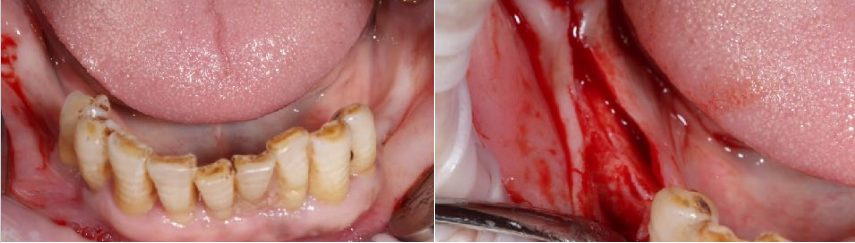

口内检查:13-23牙龈退缩,牙齿松动2-3度,14-17,24-27缺失,牙龈颜色质地正常。36,37,45,46,47缺失,下颌余留牙松动1-2度。

导板引导下种植手术:

上颌植入6颗中科安齿种植体